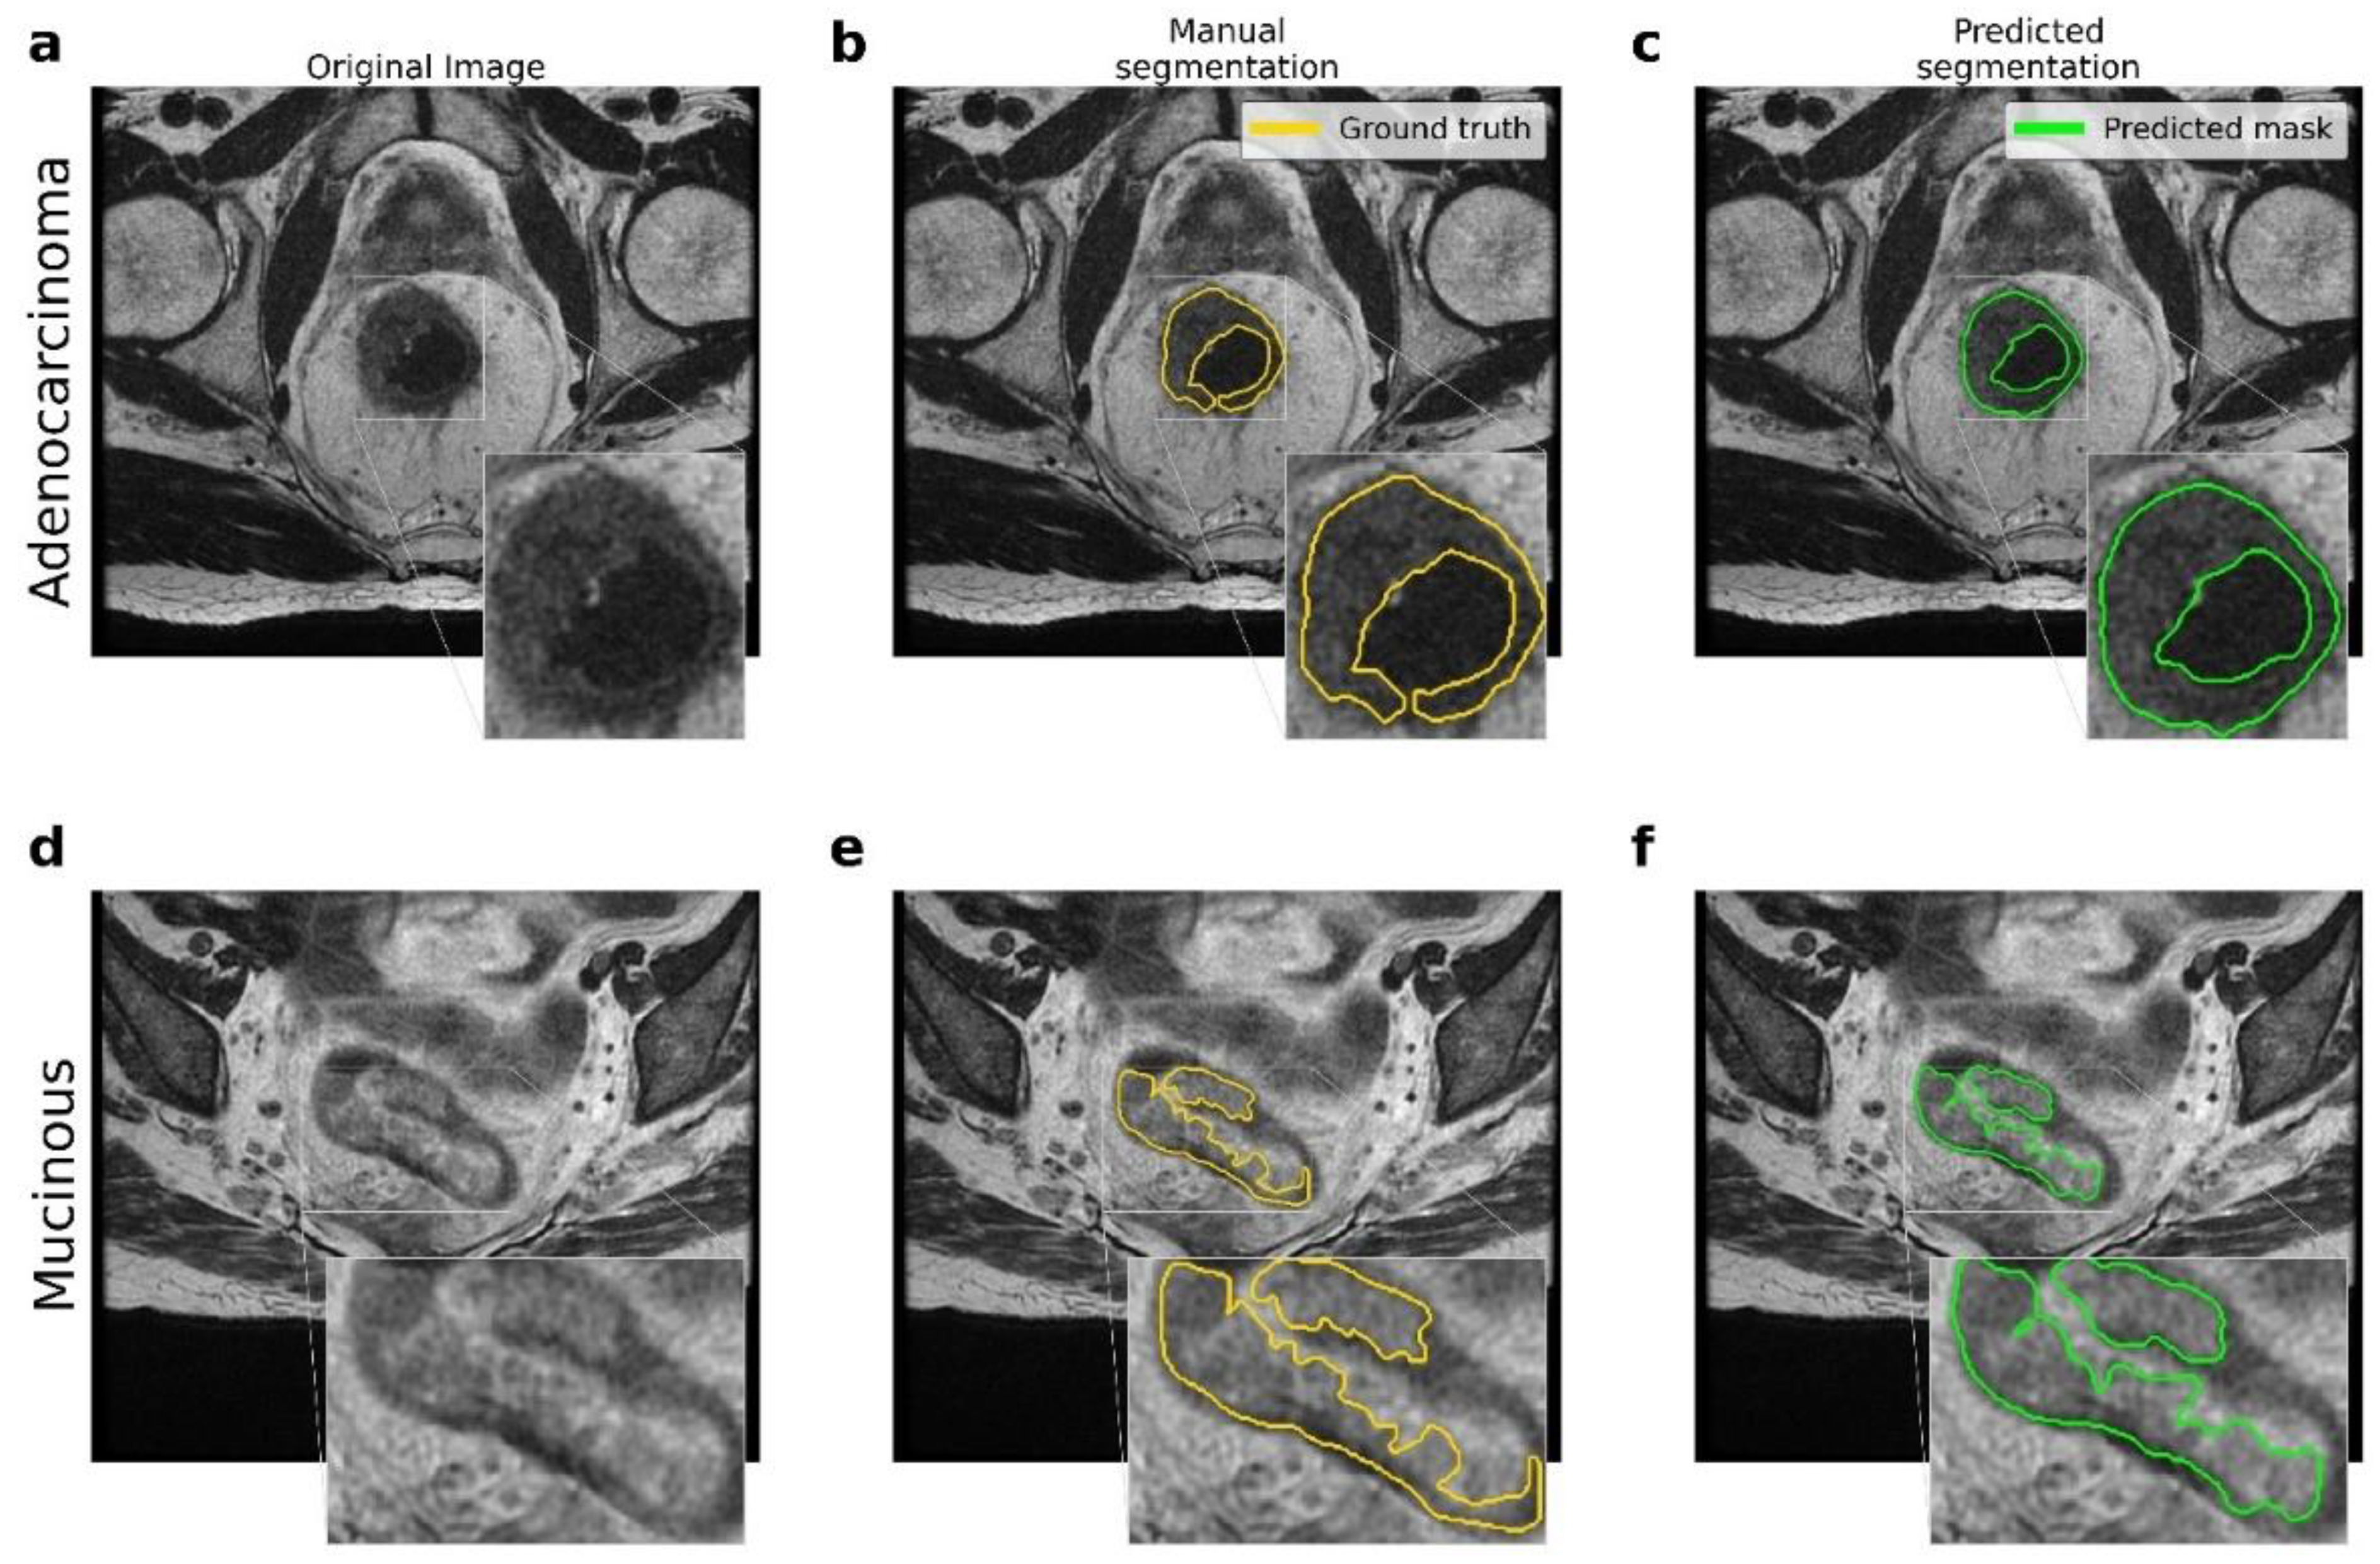

Figure 2 shows the resulting segmentations obtained by the U-Net model. The comparison between the original (raw) image, the manual segmentation performed by an expert radiologist, and the segmentation resulting from the application of the proposed U-Net model are reported. In addition, there were significant differences between the two types of lesions involved, namely adenocarcinoma and mucinous carcinoma: in T2-weighted images, mucinous rectal cancers appeared as significantly hyperintense compared to adenocarcinoma neoplasms.

Figure 2.

Comparison between the ground truth and the results obtained by the proposed pipeline for the lesion segmentation. (a–d) Original MRI scans for adenocarcinoma and mucinous cases. (b–e) Ground truth obtained by manual segmentation performed by experts. (c–f) Predicted segmentation obtained by the proposed U-Net model.